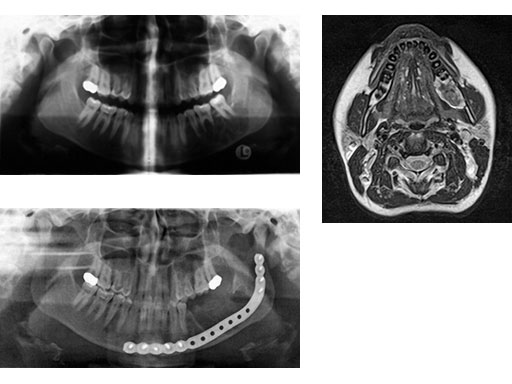

Case 1: A 27-year-old woman with an odontogenic myxoma in the left mandible. The preformed reconstruction plate was inserted prior to the tumor resection using a transoral approach with only a small additional transbuccal incision. To date the patient is free of symptoms with no signs of hypoaesthesia of the mandible and no signs of relapse. After another relapse-free period dental implants are planned for oral rehabilitation.

Fig 1 ad Transoral application of preformed reconstruction plate before tumor dissection.

Fig 2

ab Preoperative radiograph and MRI.

c Postoperative radiograph.

Case provided by Christoph Pautke, Mnchen, Germany